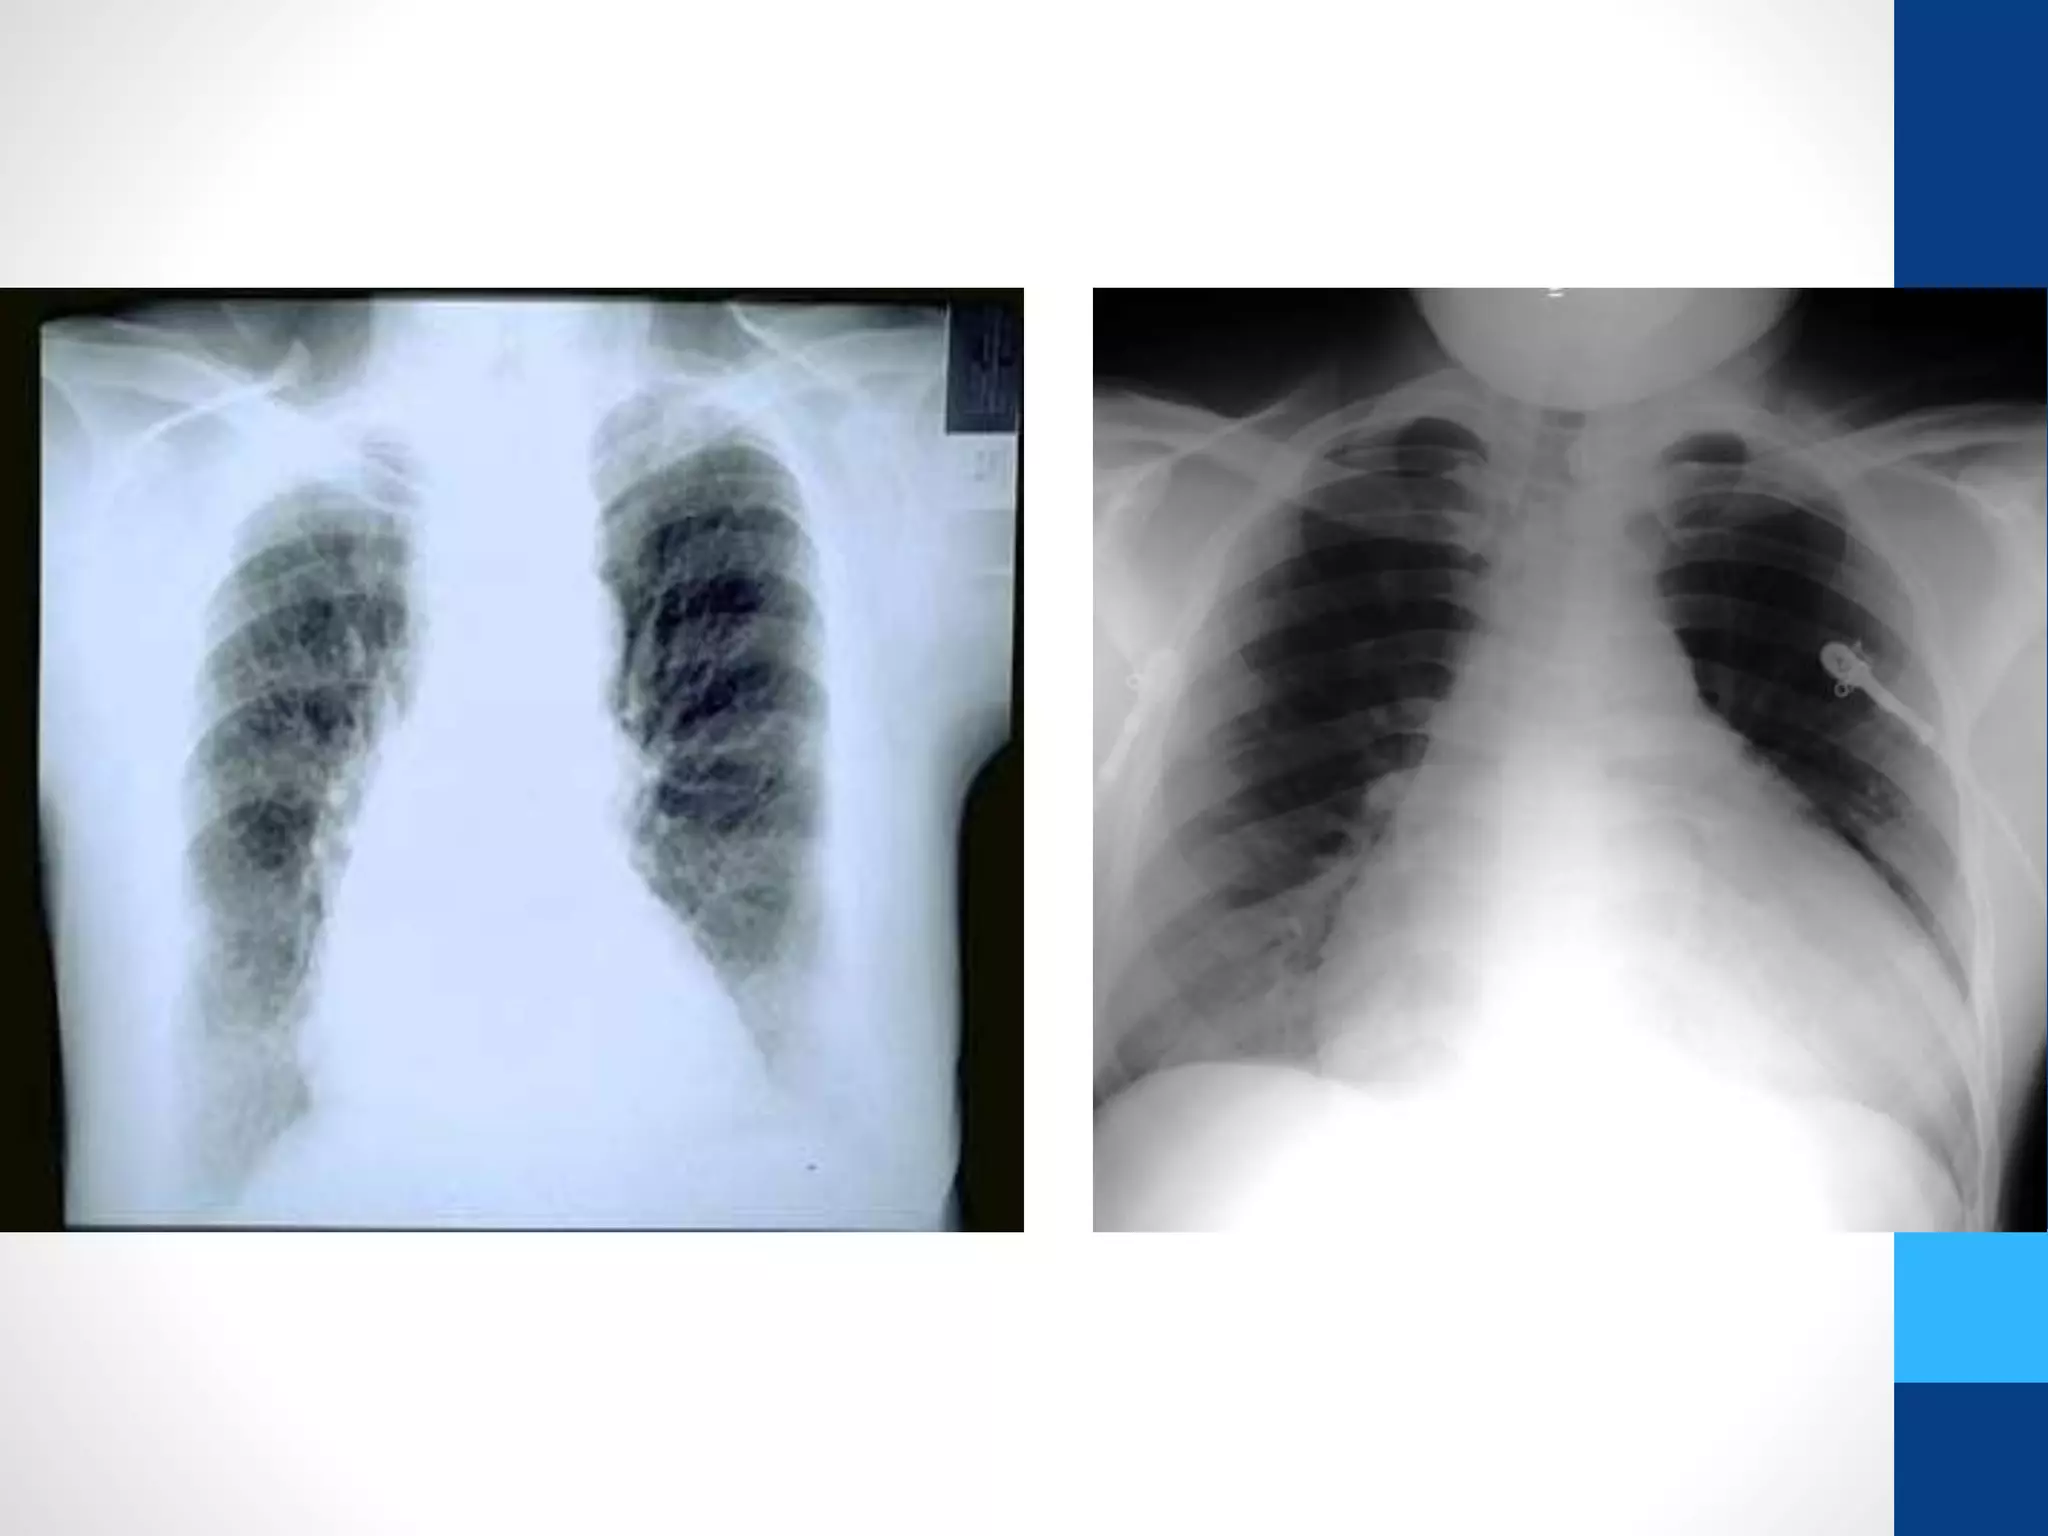

The chest X-ray showed enlarged cardiac silhouette with cardiothoracic ...

Chest X-ray showing enlarged cardiac silhouette with cardiothoracic ...

Chest X-ray with ICT=0.6. | Download Scientific Diagram

Chest X-ray in posterior-anterior view showing enlargement of the ...